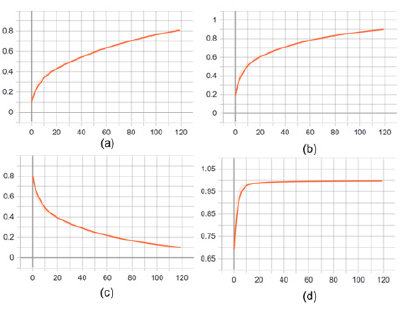

This paper builds a segmentation model of trabecular meshwork on the basis of U-Net network, and realizes the segmentation of trabecular meshwork image through pixel-by-pixel classification of the image. Due to the simpler and more intuitive advantages of keras to build a model, the unet model implemented here can not only deal with dichotomous problems, but also multi-class segmentation problems. The partial results of image segmentation of trabecular meshwork are shown in Figure 2. At present, there are many risks in the treatment of glaucoma, so it is urgent to find new methods to restore or replace the damaged trabecular meshwork. Therefore, it is very important to study the structure of trabecular meshwork. The image segmentation method based on deep learning was used to further study and analyze the trabecular meshwork, which laid a morphological foundation for the subsequent research on clinical diagnosis. The default parameter optimization model of Adam algorithm is used in the research. The initial learning rate of the model is 0.001, and the learning rate is dynamically adjusted during the training process. The batch size batch is set to 6. During the training process, the validation set loss passes through 119 steps, 42 epochs no longer decline and stop. The IoU(Intersection over Union), Dice coefficients, cross-entropy loss curve and acc change curve obtained from the Tensorboard visualization training process are shown in Figure 3, As shown in Figure 3, the light-colored lines in the figure are the original data curves, and the dark lines are the smoothed curves. The performance indicators used for image segmentation are IoU and Dice Coefficient. IoU is an index used to evaluate segmentation performance. The calculation method is: IoU = overlapping part/(real label + actual segmentation result).

The Dice Coefficient is used to evaluate the similarity between the segmentation result and the real label. Dice Coefficient = 2*predicted correct result/(predicted result + actual result). From Figure 2d, after 119 steps (42 epochs), the IoU is 0.8086, the accuracy acc is 0.9977, and the loss and dice coefficients are 0.101 and 0.8976, respectively, indicating that the model segmentation accuracy is more accurate and the training effect is better 3.3 Porosity of trabecular meshwork. When the TM inner layer was set at 0 μm, the porosity of the TM decreased with its increasing depth (in the flow direction). As shown in Figure 4a, the porosity of the TM with normal IOP was slowly decreased. While under the condition of elevated IOP Figure 4b, it was descending quickly. Additionally, the porosity of the TM in rat eyes with high IOP was less than that in the normal IOP group from the depth of 30 μm to the depth of 60 μm. Under the condition of elevated IOP (7.98 kPa), the porosity of the TM in the superficial region of the TM was rapidly decreasing from 0.65 to 0.31 and decreased from 0.31 (depth 30 μm) to 0.05 (depth 40 μm) in the deeper TM tissue adjacent to the SC. The TM tissue in the high IOP group exhibited the structures of compressed collagen fibres, and the total thickness of the TM decreased compared with the controls. It is indicated that the TM tissue can be collapsed by fusing into surrounding tissues due to the function of elevated IOP. In addition, the findings demonstrated that the changes in the TM tissue in pressurized eyes are large enough to lead to the increased outflow resistance.

Figure 3: Performance index and evaluation index of image segmentation.

a. IoU coefficient variation curve.

b. Dice coefficient variation curve.

c. Cross entropy loss change curve.

d. Accuracy rate change curve.